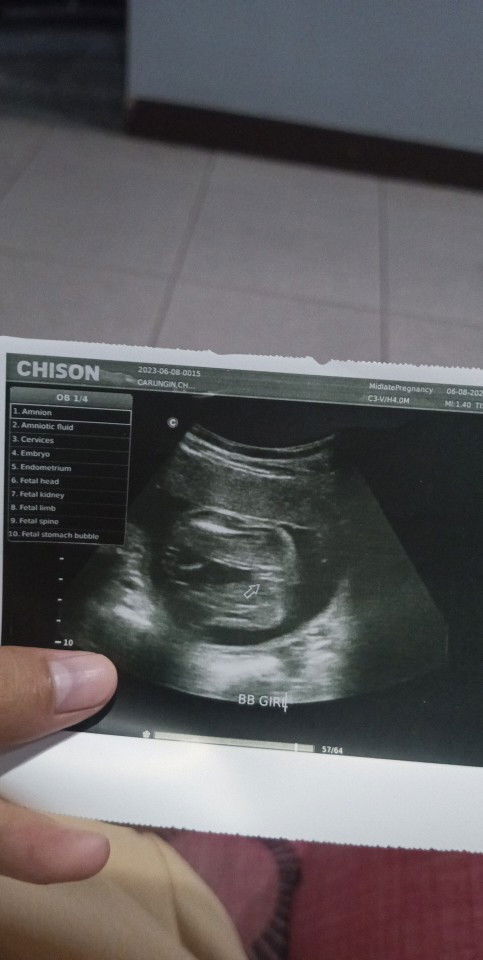

Sure na ba na girl to mga mhie?

Mga mi tanong ko lang sure na ba na girl yung baby ko kase suhi po kase nung nagpa ultrasound pero sabi doc big chance na babaw daw kase pangalawa ko na to na ultrasound para sa gender kase nung una di pa masyado makita pero sabi ni doc na possible na babae daw. 23 weeks na po ako ano p dapat gawin para maging cephalic ulit si baby? Thank you po #babygirl#suhi